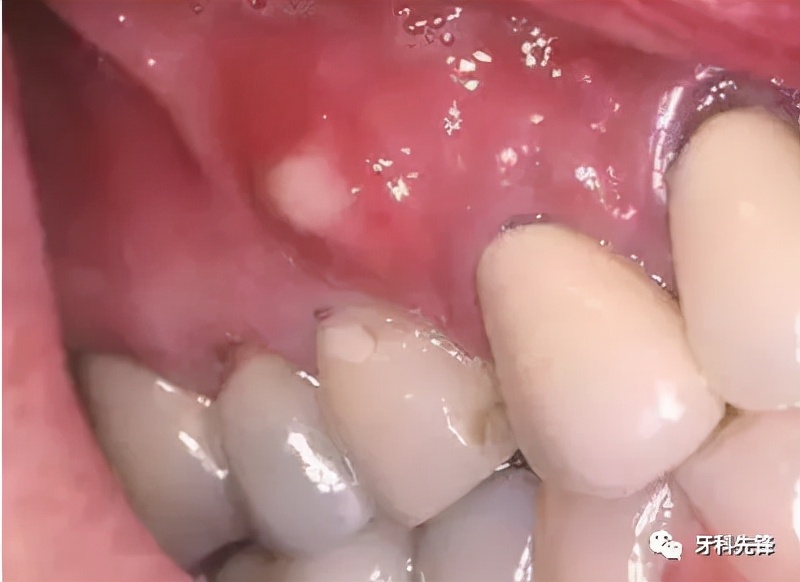

2)牙周炎

牙龈炎进一步发展成为牙周炎症,形成牙周袋,也会引起牙龈流白色的脓液。